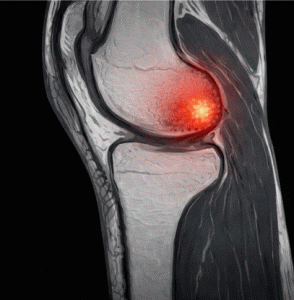

El síndrome de estrés tibial medial (MTSS, por sus siglas en inglés) es una causa habitual de dolor en la cara interna de la tibia. Afecta a deportistas, especialmente corredores de media y larga distancia, y puede limitar significativamente el rendimiento.

Se caracteriza por un dolor difuso, no puntual, que aparece al correr y puede persistir incluso en reposo si no se trata adecuadamente.

La teoría tradicional apuntaba a un desequilibrio entre el impacto repetido y la capacidad de adaptación del hueso. Sin embargo, investigaciones recientes como la de Naderi et al. (2020) indican que una actividad muscular anómala, especialmente del músculo sóleo, podría estar implicada en la aparición de esta lesión.

El estudio utilizó electromiografía de superficie (EMG) para medir la actividad del sóleo durante la fase de apoyo en carrera. Se observó que las personas con mayor activación de este músculo presentaban mayor riesgo de desarrollar MTSS.

Este hallazgo sugiere que no solo el impacto o la técnica influyen, sino también cómo trabaja la musculatura estabilizadora profunda del tobillo.

Una activación elevada y sostenida del sóleo puede generar una tracción repetida sobre el periostio tibial, facilitando la aparición del síndrome.